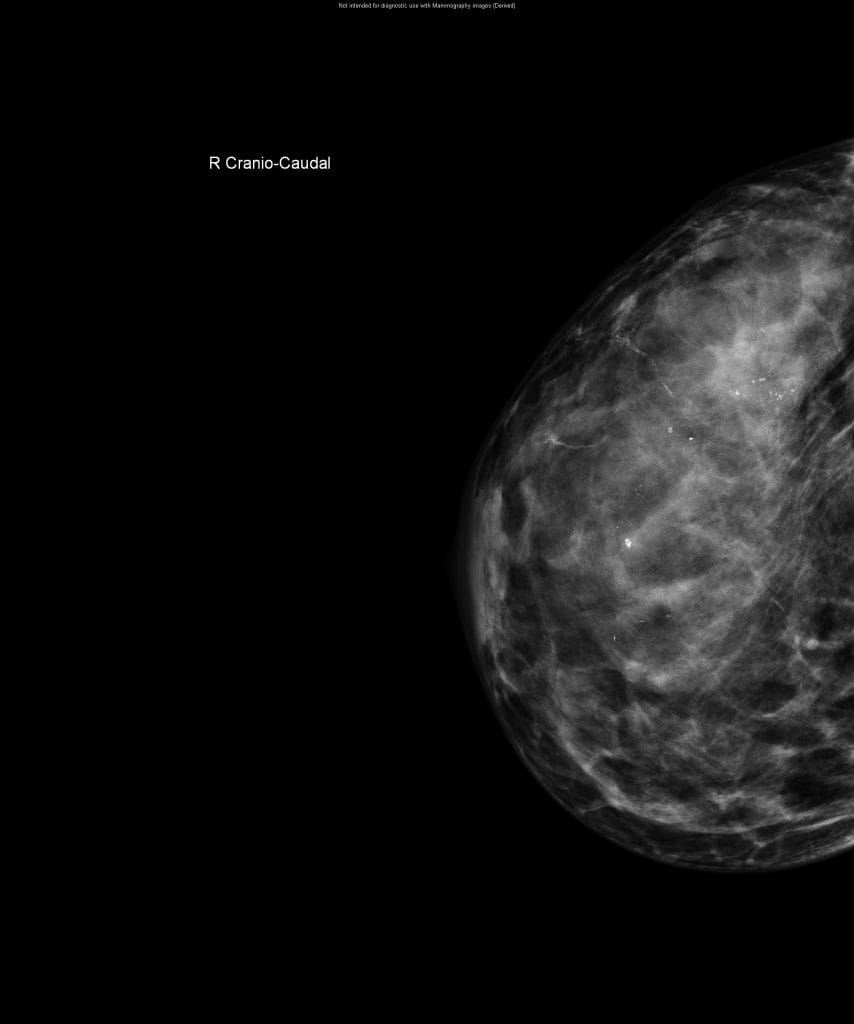

CESM is an advanced form of mammography that uses a safe dye injected into the bloodstream. This dye highlights areas of concern within the breast, giving clinicians a much clearer and more detailed image than a traditional mammogram.

“Sometimes it can be difficult to interpret a mammogram, especially in patients with dense breast tissue”, Nicole explains. “It’s a bit like looking for a cloud in a sky full of clouds. The contrast helps remove that ‘noise’ and shows us exactly what’s going on inside the breast.”